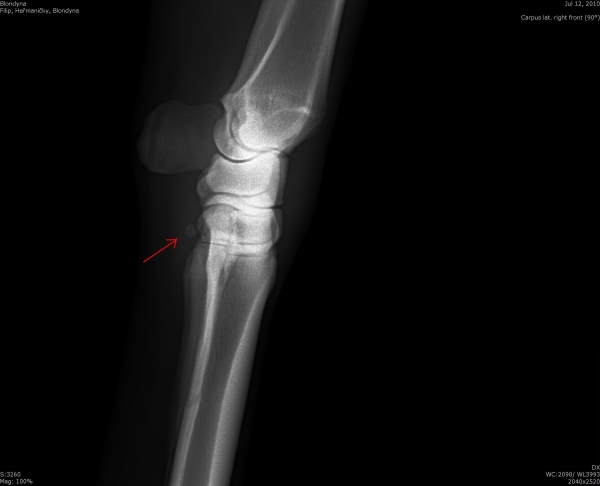

Fragment na spěnkové kosti